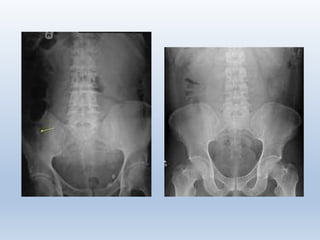

Pada foto polos biasanya sulit untuk mendiagnosis penyakit ini, biasanya kita

hanya melihat gambaran ileus, appendikolith, abses dengan efek massa dan

atau kadang disertai air collection

Foto polos abdomen dengan apendiksnormal Apendikolith pada foto AP abdomen quadran kanan

bawah pada anak perempuan 10 tahun